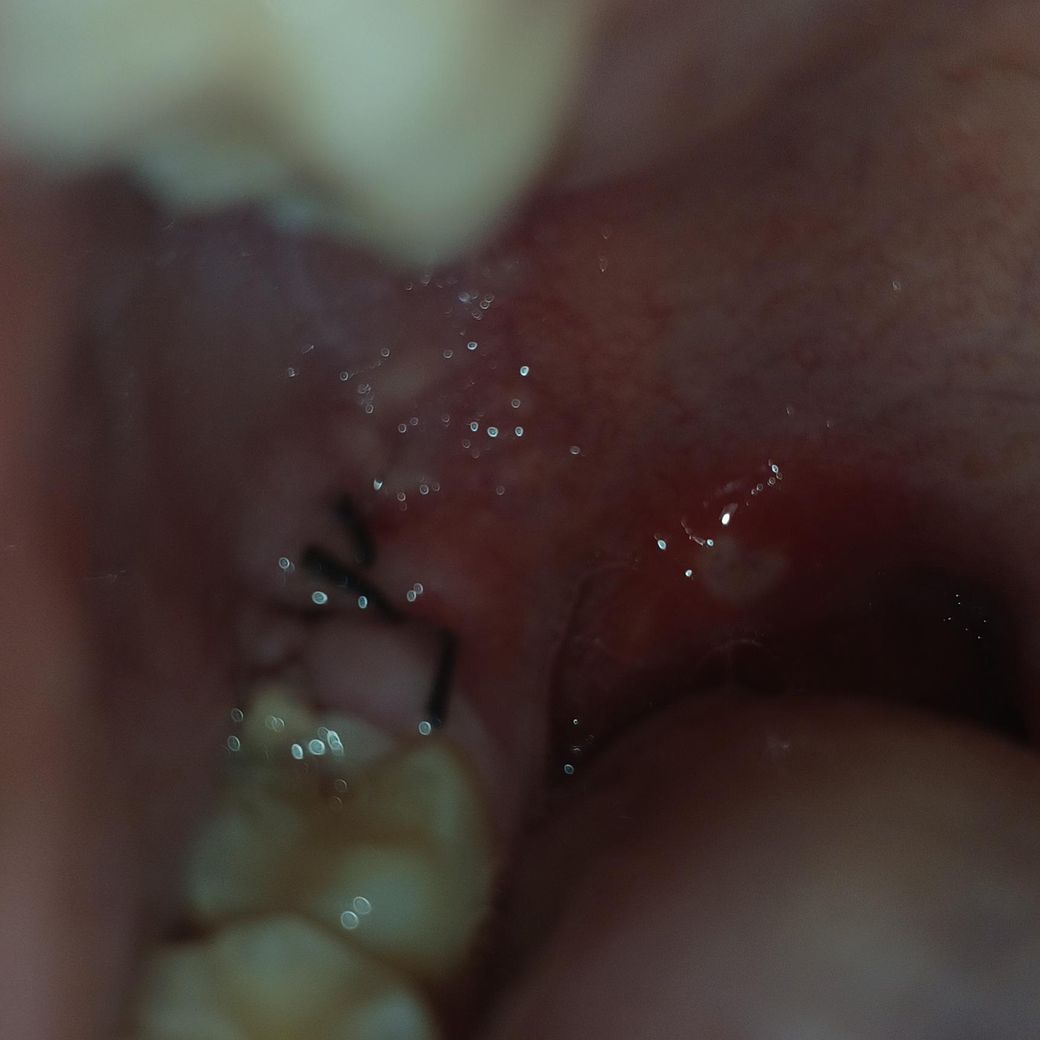

매복 사랑니 발치 했는데 잘 아물고 있는건가요?

사랑니 뽑은곳이 살짝 부은것처럼 되있고 뒤쪽에 흰색깔이 무언가가 오돌토돌하게 나와있는게 보이고 구내염이 났어요 제가 알약을 엄청 작은것도 트라우마 때문에 절대 못먹어서 항생제를 못먹었는데 병원에 가도 이미 나간약이 있기 때문에 바꾸기 어렵다고 하더라고요 지금 잘 치유되고 있는 상태인가요? 아니면 병원가서 항생제 주사라도 맞는게 좋을까요?

사진상으로 발치를 한곳이 잘 아물고 잇습니다. 최대한 자극만 가지 않도록 해주시면될것같습니다.

아직 삼일째 이기 때문에 약간의 붓기나 발적은 보이지만 전반적으로 잘 낫고 있어 보입니다.

정상적으로 아물고 있는 과정으로 보입니다. 잇몸이 불규칙하게 아물기 때문에 부위 마다 각각 다르게 보입니다. 실밥 풀고 시간 지나면 점점 편평해 집니다.

현재 사진상으론 치유에 특별히 문제가 없어보입니다. 치유 과정에서 생기는 염증, 육아조직이 희게 보일 수 있습니다. 항생제도 드시면 좋습니다.

사진으로 봤을 경우에는 정확하지는 않지만 크게 문제가 없이 아물고 있는것으로 보입니다.